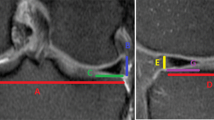

Bony posterior tibial slope

To ensure reliable and reproducible measurements, a standard protocol was applied by all observers. On a split screen the coronal, sagittal, and axial images were displayed, and the scout line and localizer mode were used to scroll through all three planes simultaneously. The annotation tools were then used to establish the centre of the tibial plateau on the axial image. The corresponding coronal image was defined as the reference image and the vertical intermediate line (yellow) defined the centre of the knee, dividing the tibial plateau into a medial and lateral half (Fig. 1). A second line (blue) was then drawn from the lateral to the medial border of the tibia, passing through the most inferior aspect of the tibial plateau. The annotation tools were then again used to establish the distance between the medial and lateral borders of the plateau. Parallel lines were drawn 25, 50, and 75% from the outer margin of the tibial plateau (Fig. 2). The corresponding sagittal images were used to measure both the bone and meniscal slopes in these three anatomic locations (Fig. 3). The proximal tibial anatomic axis (red line) was drawn by establishing two lines (blue lines), 2 and 4 cm distal to the joint line, and connecting the midpoint between these two lines (red line) (Fig. 3). The tibial plateau was marked with a line from the most anterior to the most posterior point of the tibial plateau (yellow line) (Fig. 3). The slope was measured between the tibial plateau (yellow line) and a line that was established 90° to the proximal tibial anatomic axis. If the slope was directed posteriorly it was defined as posterior or negative (−), and if the slope was directed anteriorly it was defined as anterior or positive (+).

The annotation tools of the PACS Impax were used to establish the centre of the tibial plateau. The tools allow simultaneous shifting of reference lines in all three images. The corresponding coronal image was defined as the reference image and the vertical intermediate line (yellow) defined the centre of the knee, dividing the tibial plateau into a medial and lateral half

In this step, the most medial and lateral aspects of the joint line were marked with a vertical line (blue line). A line was then drawn from the joint line (blue line) to the centre of plateau passing through the most inferior aspects of the plateau (yellow line). The annotation tool is then used to draw three parallel lines 25, 50, and 75% of the distance across the joint line (red lines)

The proximal tibial anatomic axis (PTAA) was established by drawing two lines on a sagittal image, 2 cm apart, from anterior to posterior (blue lines). The midpoint between these two lines was connected, resulting in a vertical line (red line) that is defined as the PTAA. The tibial plateau was defined by a line drawn from the most anterior to the most posterior point on a sagittal image (yellow line). An additional perpendicular line (green line) to the PTAA was drawn from the point where the tibial plateau line meets the PTAA. The angle between this line (green) and the tibial plateau line (yellow) has been defined as the posterior tibial slope. The slope was defined as posterior (−) if the plateau line is inferior to the perpendicular line, and anterior (+) if the plateau line is proximal to the perpendicular line

Meniscus slope

To establish the meniscus slope of the posterior horn, a line was drawn across the superior surface of the meniscus between the most posterior and the most proximal point of the meniscus, tangent to its superior surface (red line) (Fig. 4). The angle between the meniscus line and tibial plateau was then defined as the slope of the posterior horn of the meniscus (Fig. 4). The combined resultant slope was calculated by adding the meniscal slope to the bone slope. Similar to the bone slope, a posteriorly directed slope was defined as posterior or negative (−), and anterior or positive (+) if the slope was directed anteriorly.